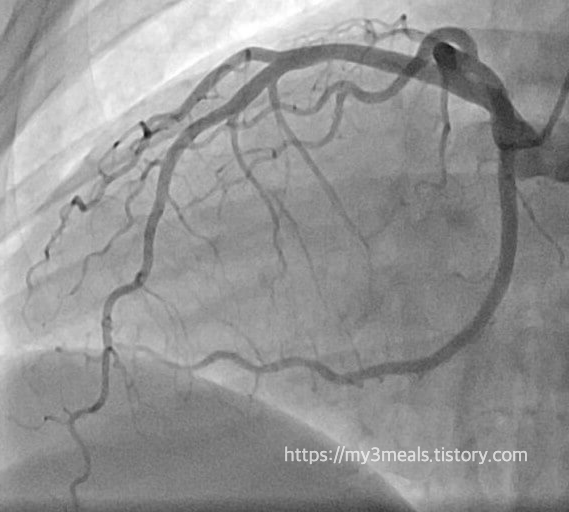

심장 조영술

병원에 도착한 후 아버지는 곧바로 심장 조영술을 받았고, 그 결과 막힌 혈관을 확인했습니다. 의료진은 즉시 관상동맥 중재술을 시행하여 막힌 혈관에 스텐트를 삽입해 혈류를 다시 원활하게 했습니다. 이 과정은 매우 빠르게 이루어졌고, 덕분에 아버지는 심각한 합병증 없이 심근경색에서 회복하실 수 있었습니다.